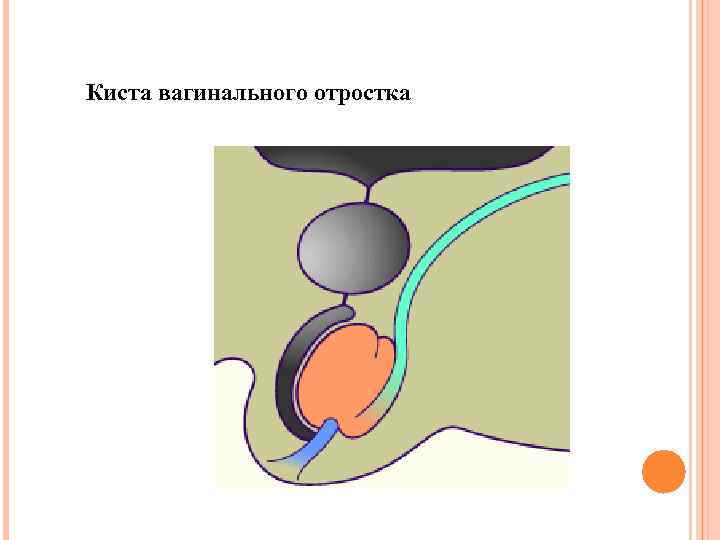

Киста вагинального отростка

Киста вагинального отростка